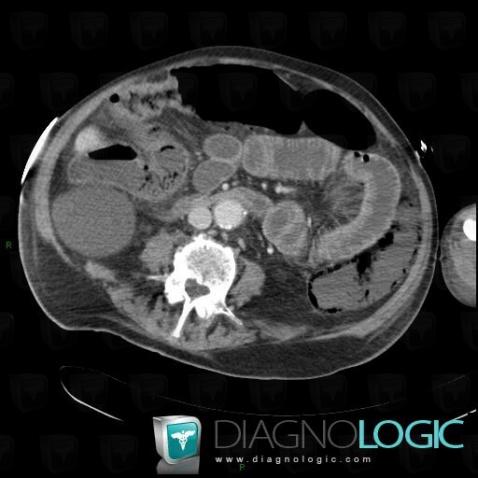

Portal venous gas, Portal vein and branches, CT

Here is the specific information in the key image above:

- Diagnosis Portal venous gas, Location(s) Portal vein and branches, with gamuts